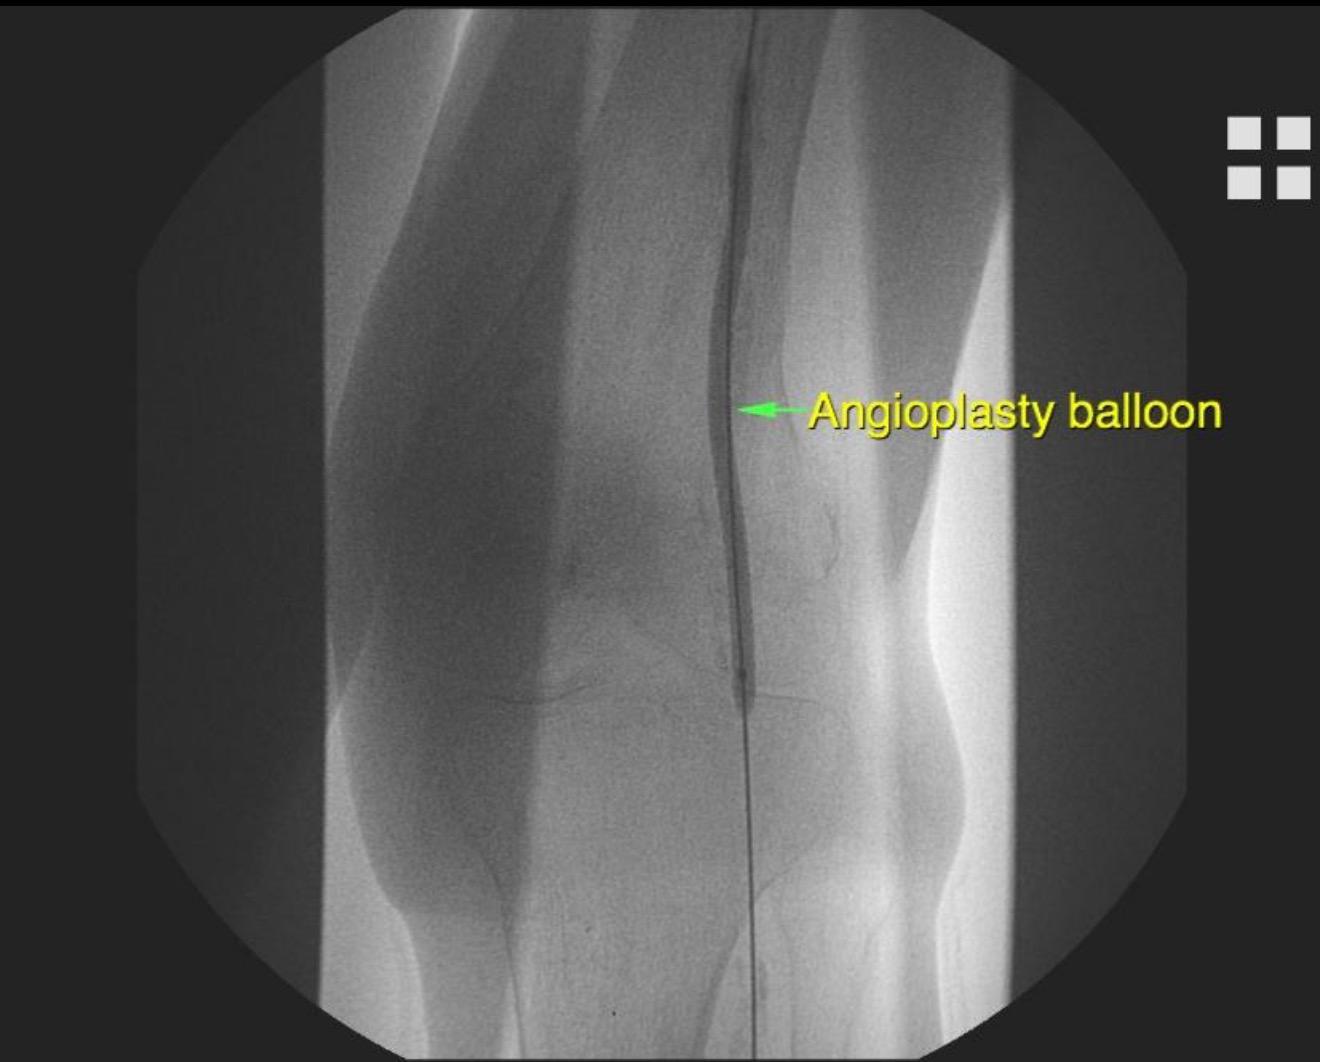

4️⃣ Tedavi (gerekirse aynı anda)

Anjiyo sırasında damar açma işlemi yapılabilir:

* Balon anjiyoplasti

* İlaçlı balon

* Stent yerleştirme

* Aterektomi